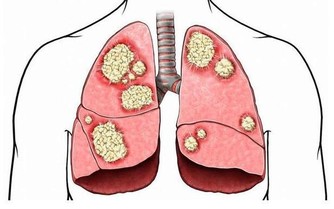

4、按摩的地方沒有感染、嚴重的皮膚病,如各種急性傳染病,急性骨髓炎,結核性關節炎,傳染性皮膚病,皮膚濕疹,水火燙傷,皮膚潰瘍,腫瘤,以及各種瘡瘍等。